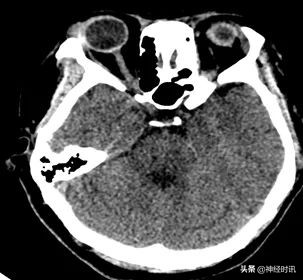

CT检查

脑干可见片状高密度影,测其最大层面约18 mm×15 mm× 20 mm,CT值约65 HU。脑室系统未见明显扩大及变形,脑沟脑裂显示清,中线结构居中。结合CT计算脑干出血量约3 ml。

急诊CT

初步诊断:1.脑干出血;2.高血压病3级 (很高危)。

诊断依据:青年女性患者急性起病,意识不清。颅脑CT示:脑干出血。